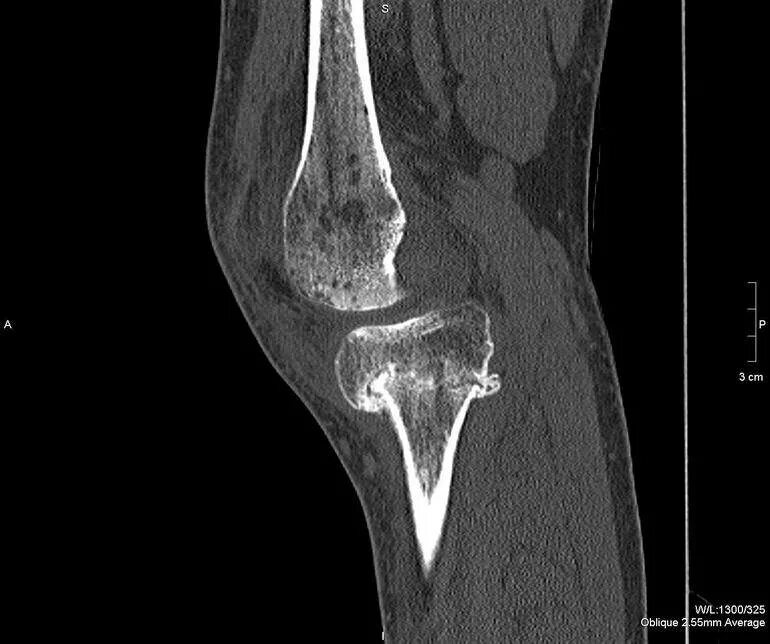

Кт суставов что показывает